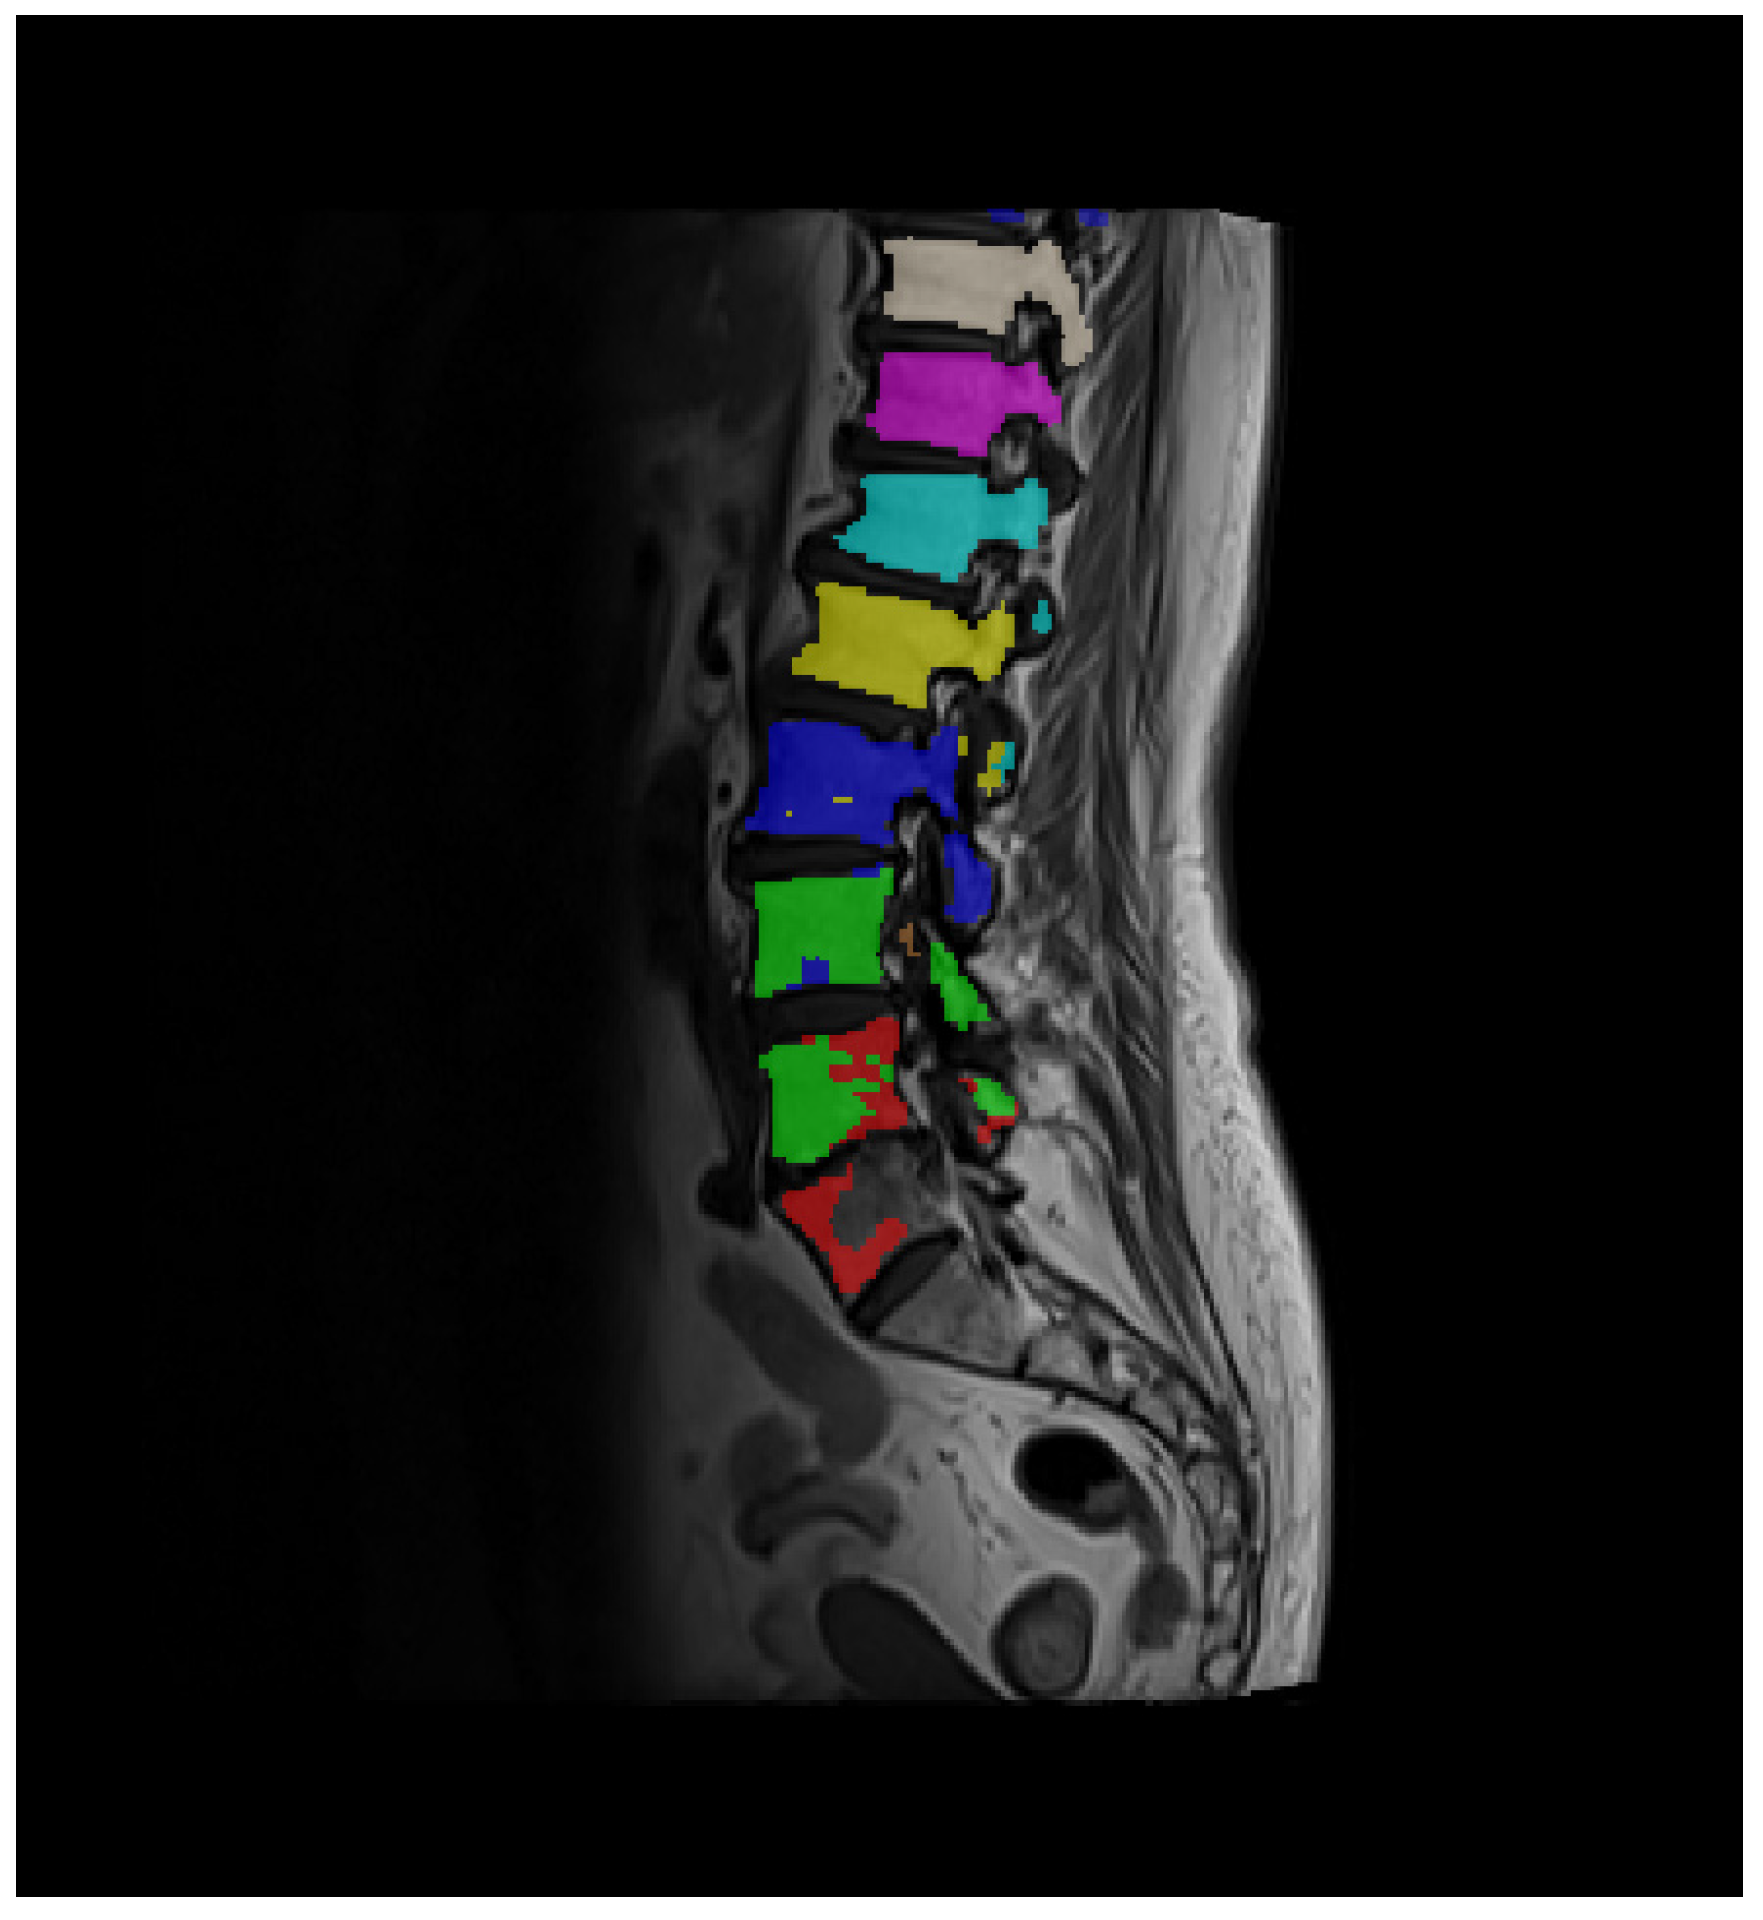

Even though the trained model performed well according to the evaluation metrics presented in Table 1, for some of the 166 series data chosen for VBQ determination, a mixing of segmentation labels is present in the prediction provided by the trained model. An example of segmentation label mixing is shown in Figure 5.

Figure 5. An image slice example showing mixing of labels (green/red and blue/yellow). Different colors represent each of the 9 segmentation classes, which are labeled 1–9 in the segmentation masks.